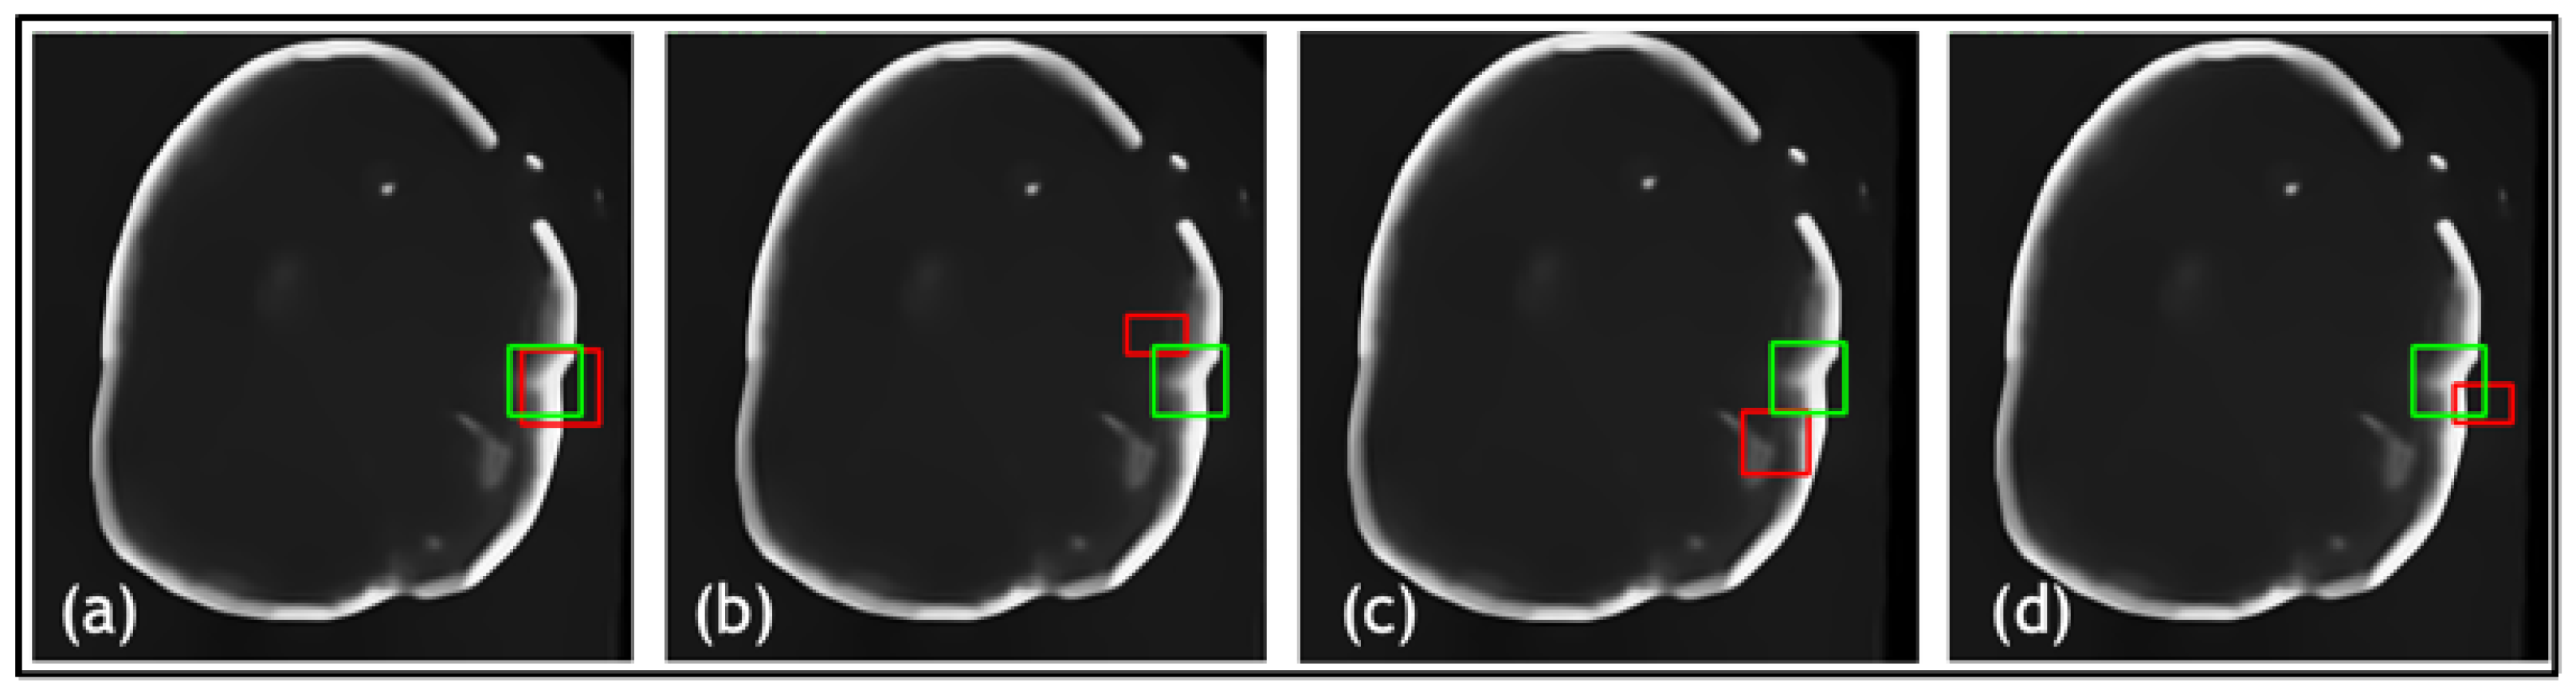

- A novel TED framework is developed, focusing on detecting relevant lesions in noisy OCT images of different organs.

- In TED, the transformer is adapted to take in images and slide across Regions of Interest (ROIs) provided by AGs. This design aims to adaptively deal with different types of noise artifacts and thus effectively detect a variety of anomalies including tooth decay and numerous lesions across two modalities.

- A new loss function is proposed along with TED, which combines a sliding box, Intersection Over Union (IOU), and Mean Squared Error (MSE). It compares the IOU and MSE between the predicted and real bounding boxes to evaluate the regions of focus chosen by the AGs.